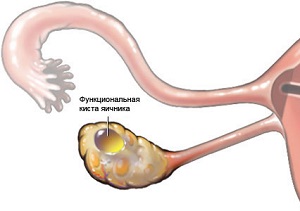

Кісти яєчників і вагітність